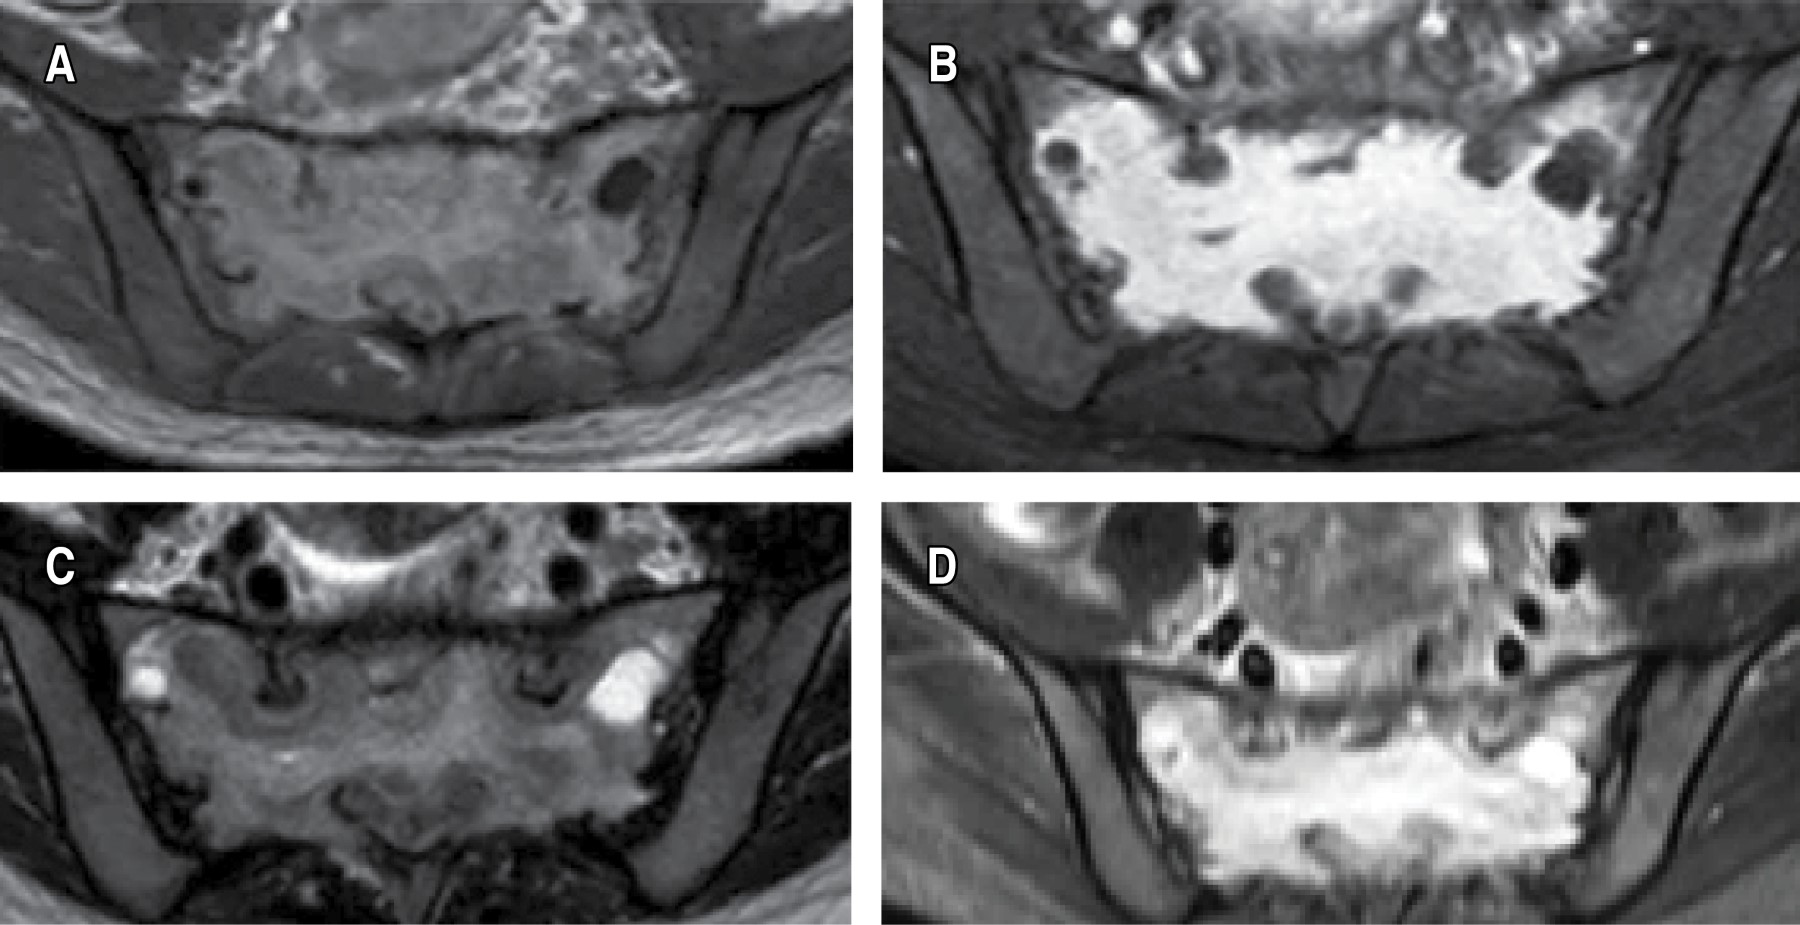

La resonancia magnética reveló que la lesión que comprometía el sacro de forma difusa, era hipointensa en la secuencia T1 (Figura 2A), con realce ávido luego de inyectar el medio de contraste intravenoso (Figura 2B) y de forma heterogénea e hipertensa en las secuencias T2 y STIR (Figura 2C y 2D).

La resonancia magnética mostró un crecimiento infiltrativo en S1-S2 y ligeramente expansivo con preservación de la estructura sacra y respetando tejidos blandos, apreciándose en forma difusa y homogénea, con señal hipointensa en la secuencia T2 (Figura 5A y

La detección de un tumor sacro solitario a menudo genera una consideración diagnóstica de tumores sacros más frecuentes, como cordoma, tumor de células gigantes, condrosarcoma y tumor óseo metastásicos, antes de pensar en plasmocitoma solitario del sacro (PSS)2,4,7 más aún si los pacientes están en la edad productiva. Afirmamos que la presentación clínica es similar y con las mismas características que en los adultos mayores.2,5,6,8 Identificamos que los hallazgos de imagen en ambos pacientes tienen las mismas características en la tomografía computarizada (TC) y la resonancia magnética (RM). Verificando que los hallazgos morfológicos de imagen tienen un patrón característico, que les permite diferenciarse de otros tumores.4 Las imágenes por tomografía computarizada se caracterizaron en los dos pacientes como una lesión lítica o una lesión destructiva, de tipo esclerótico no expansible, como también lo informaron en su estudio Lanzieri y colaboradores.2,4 La resonancia magnética mostró una morfología con señal hipointensa en las imágenes ponderadas en T2 y un patrón de realce con contraste homogéneamente intenso, mostraron un crecimiento infiltrativo y ligeramente expansivo con preservación de la estructura sacra, en las secuencias sagitales el patrón de crecimiento preserva el disco intervertebral, al igual que lo describió Kosaka N y asociados,4 características que le permiten diferenciar del cordoma y del condrosarcoma donde se observa las lesiones hiperintensas en las secuencias potenciadas en T2.11 Sin embargo, en el tumor óseo metastásicos y el tumor de células gigantes, se detectan hallazgos radiológicos similares a los observados con PSS, lo que hace que el diagnóstico definitivo sea problemático,12,13 la correlación clínica puede ser beneficiosa en tales situaciones. Estableciéndose que los tumores óseos malignos del sacro, similares a los tumores de otras localizaciones en la columna, muestran sitios de manifestación y distribución por edades típicos, mientras que la región del cuerpo afectada por el tumor permaneció igual, la distribución por edades cambió a décadas anteriores en muchas enfermedades.2 Sin duda alguna, el diagnóstico definitivo es anatomopatológico, por lo que planteamos como una alternativa para la toma segura de muestra la técnica de biopsia con sistema tubular.1,2,10 El tratamiento es la radioterapia, siendo un 90% favorable;8 sin embargo, se ha informado que un inadecuado manejo terapéutico puede llevar a la progresión a mieloma múltiple e insuficiencia renal en 50% de los casos mal controlados,8,9 por lo que recomiendan una mejor monitorización de la respuesta al tratamiento, mediante imágenes funcionales con tomografía por emisión de positrones (PET/CT) con 18F-FDG y tecnecio.6,14-16 Criterios que nos orientaran a un mejor seguimiento a nuestros casos identificamos.